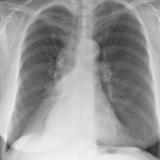

RLL Collapse 1 PA

Date: 02/28/2004

Views: 3362